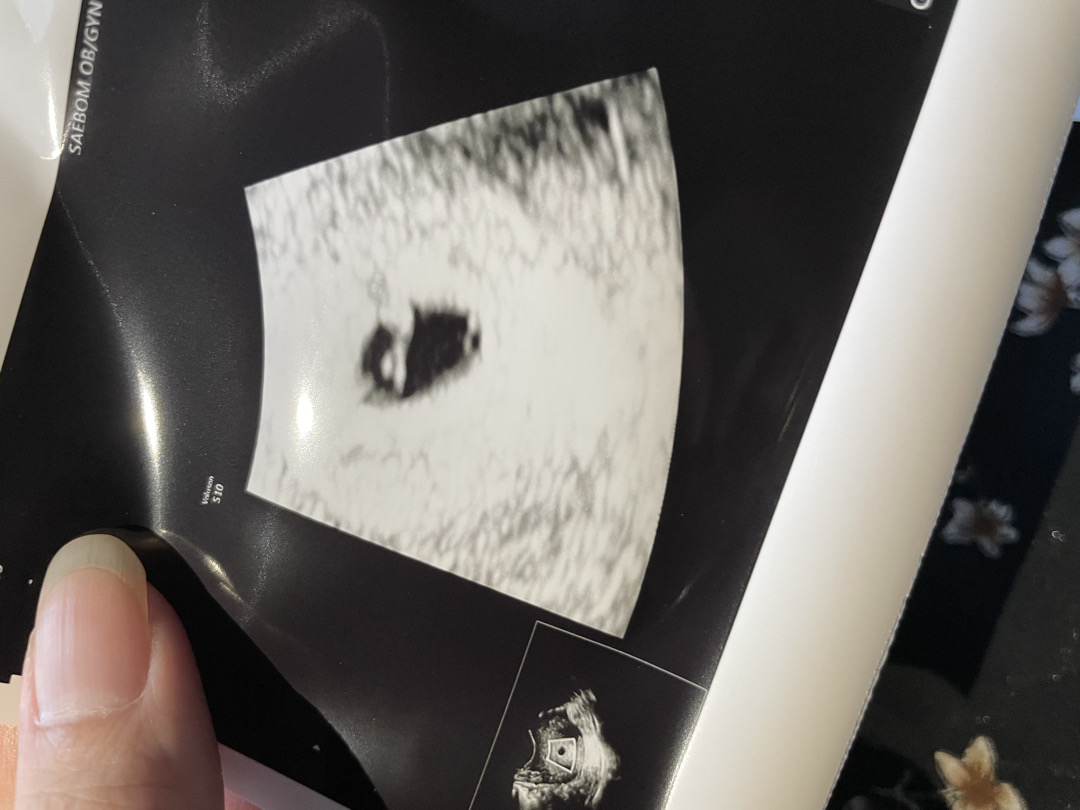

아기집을 오늘 보고왔는데 0.55정도라고 작다거 하시는데 안에는 혹시 뭔가요?ㅠㅠ생긴게 난황치고는 특이하게생겼어요 괜찮을까요

그것 못물어봤네용 ㅠㅠ 5주 2일차입니당